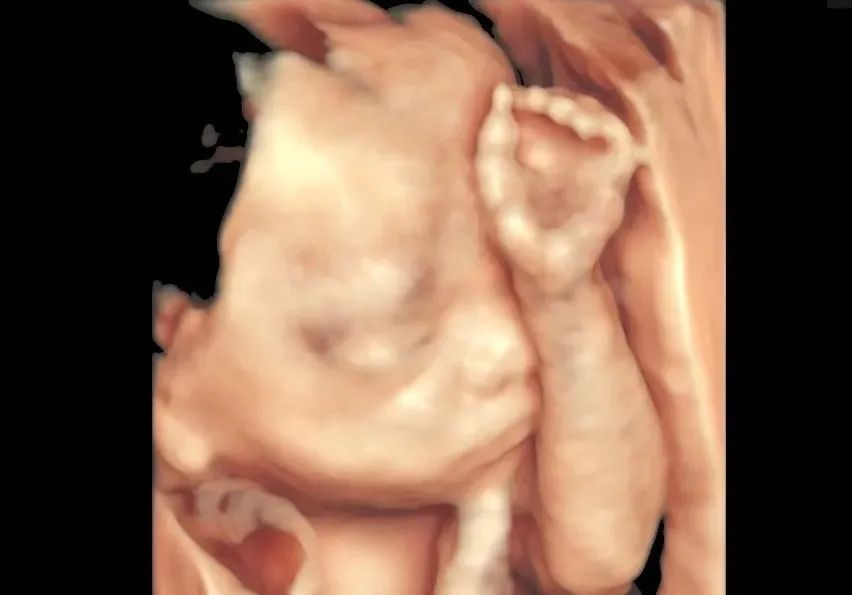

“孕22周,体重230多斤,医生说我腹部脂肪太厚,辗转几家医院都被拒之门外…”“做四维时我月份超了,胎儿偏大,有些部位看不清,如果多花时间,风险也会增加”“我怀的是双胎,在老家医院做彩超,查了一个宝宝的心脏,另一个却怎么都做不出来”四维彩超对准妈妈来说是重要的孕期检查然而有些孕妈却因为上面这些情况不得不错过这项筛查但正是这类孕妈,妊娠的风险也会更高产前超声筛查对她们而言其实更加重要8月7日徐州和平 ...

“孕22周,体重230多斤,医生说我腹部脂肪太厚,辗转几家医院都被拒之门外…”

“做四维时我月份超了,胎儿偏大,有些部位看不清,如果多花时间,风险也会增加”

“我怀的是双胎,在老家医院做彩超,查了一个宝宝的心脏,另一个却怎么都做不出来”

完成一项项看似“不可能”的超声筛查